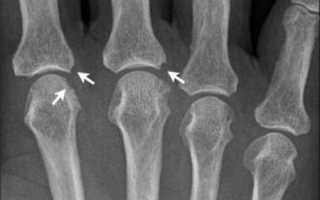

Эрозии костей при патологии

Эрозии костных структур делят на три вида:

- Краевая или поверхностная — выявляется уже на второй стадии в суставах, где отсутствует хрящевая структура и трение более жёсткое.

- Компрессионная — происходит из-за усугубления процесса и провала кости в месте повреждения.

- Деформирующая — формируется из-за разрушения костной пластины, визуально наблюдается видимая деформация кости, характерна для 4 стадии патологии.

При появлении эрозий костей излечить заболевание практически не удаётся. Длительная многокомпонентная терапия помогает лишь приостановить прогрессирующий процесс.